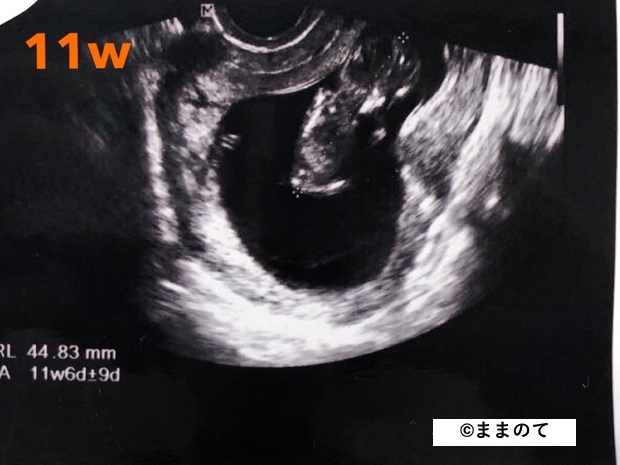

妊娠3ヶ月(8・9・10・11週)

足や手、指が形成されるのがこの時期です。胎動が始まるため、4Dエコーではぴょこんと跳ねる様子が確認できるかもしれません。

身長は約9cm、体重は20~30gにまで成長します。大人の握りこぶしやリンゴくらいの大きさです。